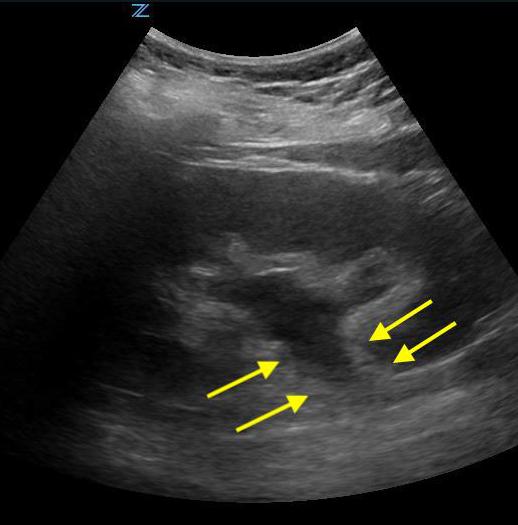

- Figure 2. Moderate hydronephrosis demonstrating location of ureter (surrounded by arrows) exiting renal pelvis

- The ureters are generally not well visualized by US, but, when distended may appear as a tubular structure extending inferiorly from the kidney

- Videos 14-15. Moderate hydronephrosis